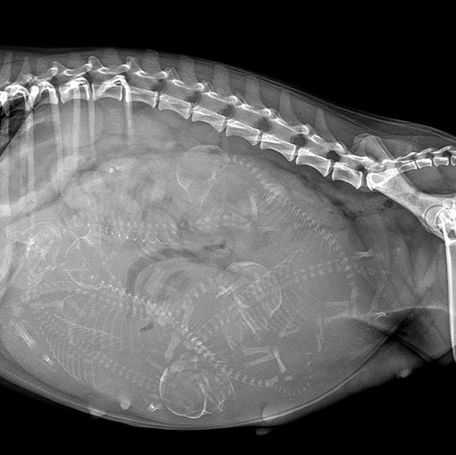

Health Screenings in Dog Breeding: Ensuring Healthy Generations

Health screenings are a critical component of responsible dog breeding. They help ensure the health and well-being of both the breeding...